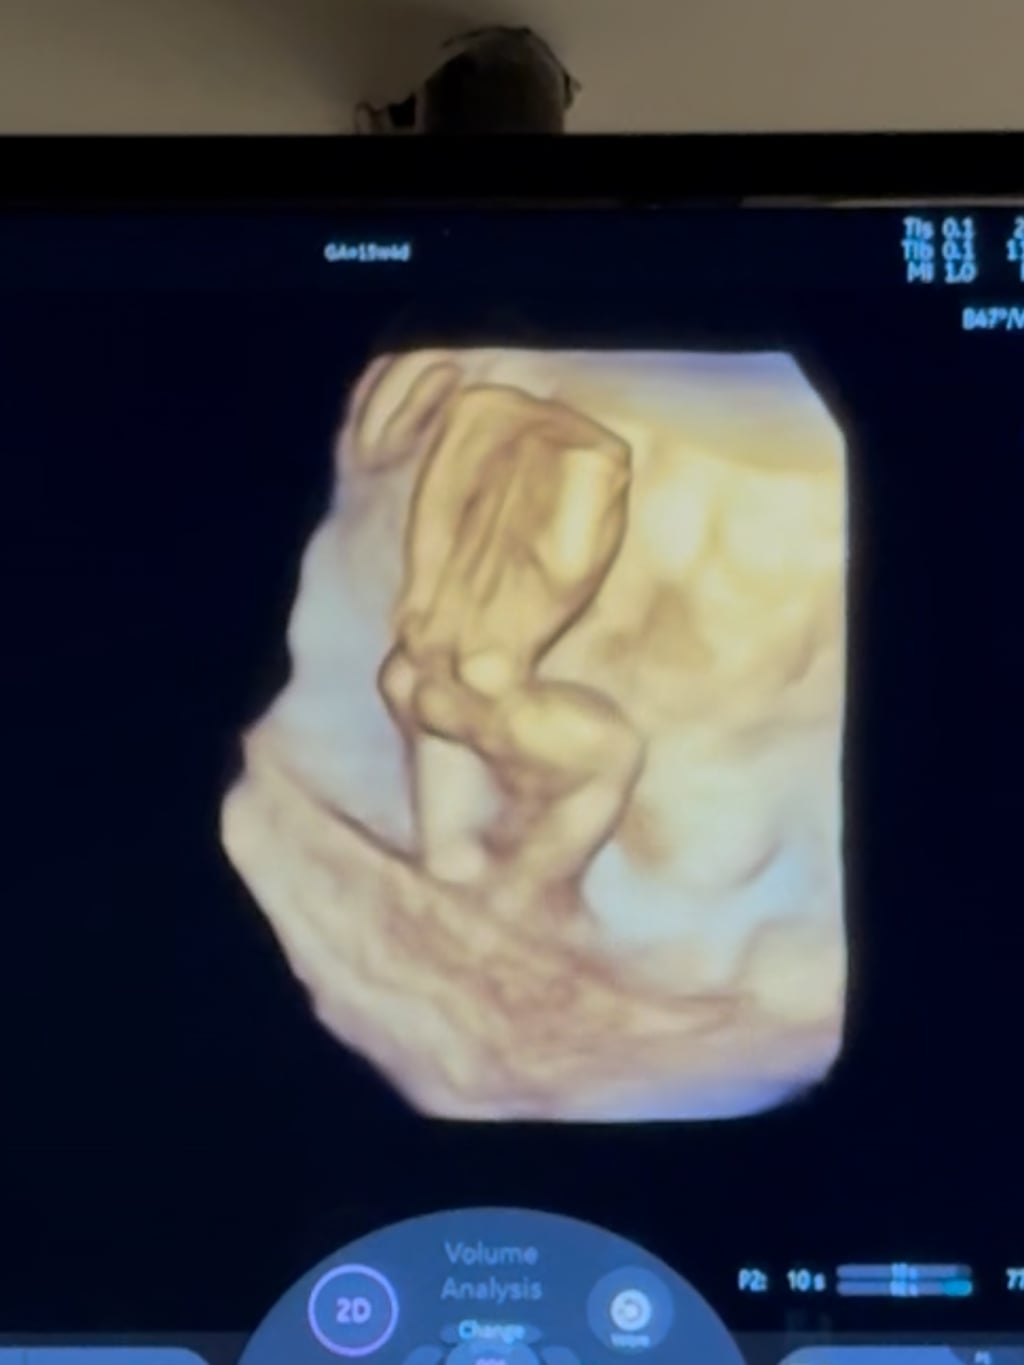

八點檔女星李又汝自2022年與圈外男友「修哥」結婚後,於今年1月喜慶宣布懷孕,目前已懷有5個月身孕。日前她特別舉辦了一場溫馨的性別揭曉派對,在親友見證下戳破氣球,露出藍色的小氣球代表「男寶寶」,夫妻倆當時還激動相擁,並為寶寶取了暱稱「小藍莓」。

沒想到,這場喜悅竟然出現「驚人翻轉」,李又汝近日受訪時透露,最近做完更精密的羊膜穿刺檢查後,醫護人員告知報告結果「是一個健康的女寶寶」,她笑說當下接到通知還以為是不是對方看錯或是搞錯,但對方確定的說沒有,她激動大喊「所以我是女兒!」真的實在太驚喜了。

不過,準媽媽的辛苦也不少。李又汝分享,孕期因舊疾復發,加上曾發生車禍導致髖關節脫臼,讓她比一般孕婦更容易感到不適,目前正透過復健與熱敷緩解症狀。儘管身體微恙,她仍充滿幸福感,期待接下來順利迎接這位「大反轉」的小公主出生。